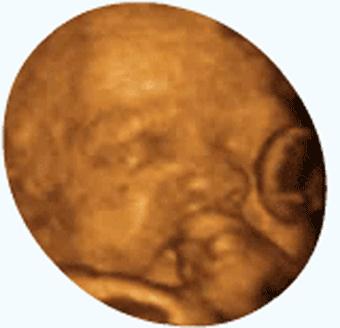

怀孕之后孕妈妈对胎儿的一举一动都是相当关心啊,经常会问出意想不到的问题,恨不能放个录像机在肚子里了。6个月时都可以去做四维彩超了,这时胎儿的样子已经接近出生时的模样,所以孕妈妈才关心6个月的动静问题吧。

6个月的胎儿从外观上看已经各就各位、形状完整,各项器官也发育完善,在肚子里的活动也游刃有余了。你知道吗?胎儿除了胎动外,还有很多更有意思的事情,一起来看看吧。

胎儿特别会做鬼脸,挤眉弄眼,玩得可欢了。最四维彩超的时候可以仔细观察一下胎儿的动作,还是蛮有意思的。